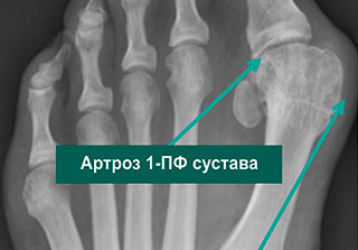

Артроз плюснефалангового сустава: причины возникновения, способы диагностики и лечения

Артроз плюснефалангового сустава, как диагностировать и лечить заболевание. Основные симптомы и признаки недуга. Перечень медикаментов для терапии.